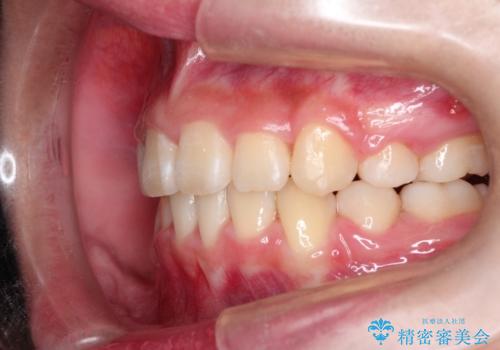

- 上下左右4本の小臼歯を抜歯、ラビアル・ワイヤー矯正を計画した。

抜歯をして第1小臼歯分のスペースを獲得することにより、ガタつきの改善と前歯のリトラクトをおこない、横顔の印象もすっきりとし、整ったEラインを作ることができました。